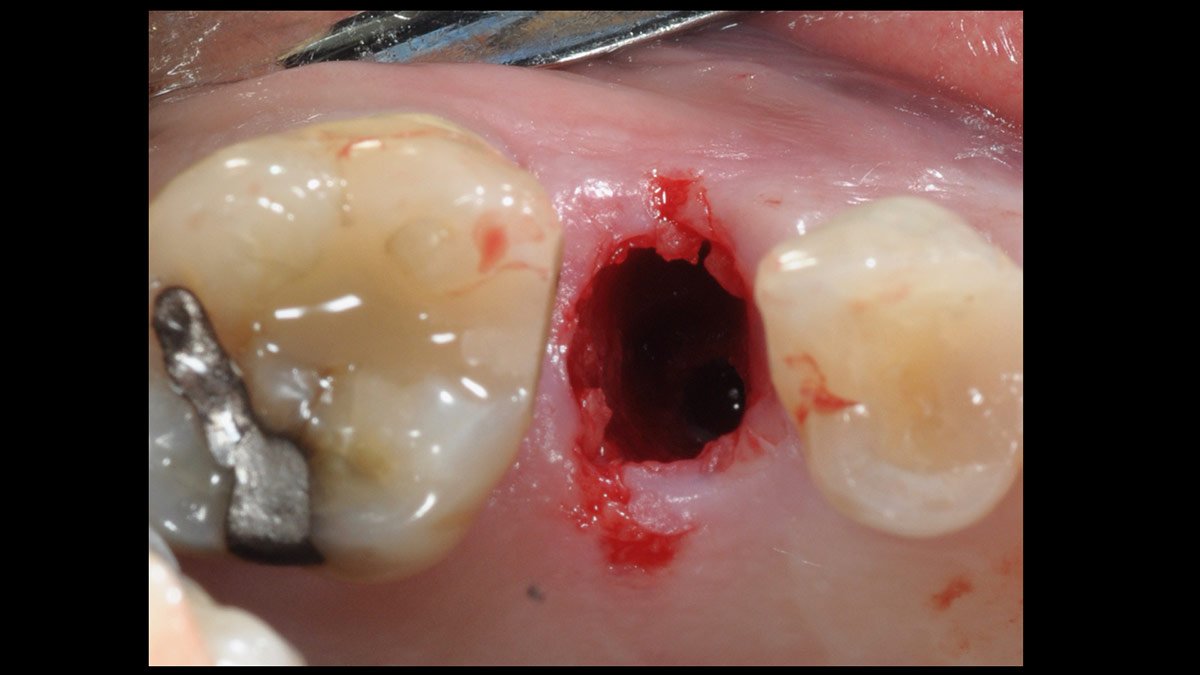

Immediate molars predictable? A case by @immediate_implantology